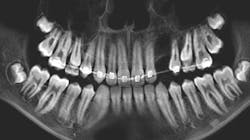

A 13-year-old male was noted by his orthodontist to have an expanding radiolucency encompassing impacted tooth no. 11. The patient was without complaint, and his medical history was otherwise unremarkable. A CT scan revealed a multilocular radiolucency extending from the maxillary midline to the area of the left permanent second molar and expanding into the left maxillary sinus. Cortical expansion in the area of the lesion was notable and all adjacent teeth were vital.